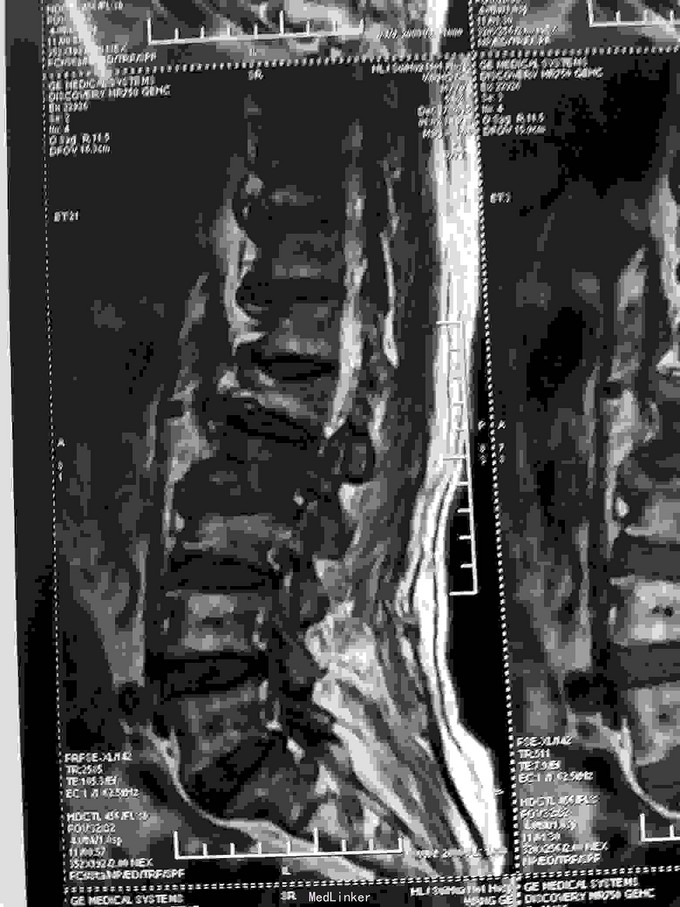

根据病史查体诊断:腰间盘突出症待确诊。应用消肿营养神经镇痛治疗。一天。查核磁共振示:腰椎多节段间盘突出伴椎管狭窄。第二腰椎骨破坏侵及椎板。部分突入椎管,脊髓受压。诊断:腰间盘突出伴椎管狭窄。第二腰椎转移癌,脊髓受压。经与家属沟通,查双肺CT:双肺下叶炎症。肺部纤维化。可见肿瘤阴影。肋骨及胸膜受累。胸椎部分骨破坏。最终诊断:双肺癌,胸椎,腰椎骨转移,脊髓受压。多节段腰椎间盘突出。病人至肿瘤科治疗。